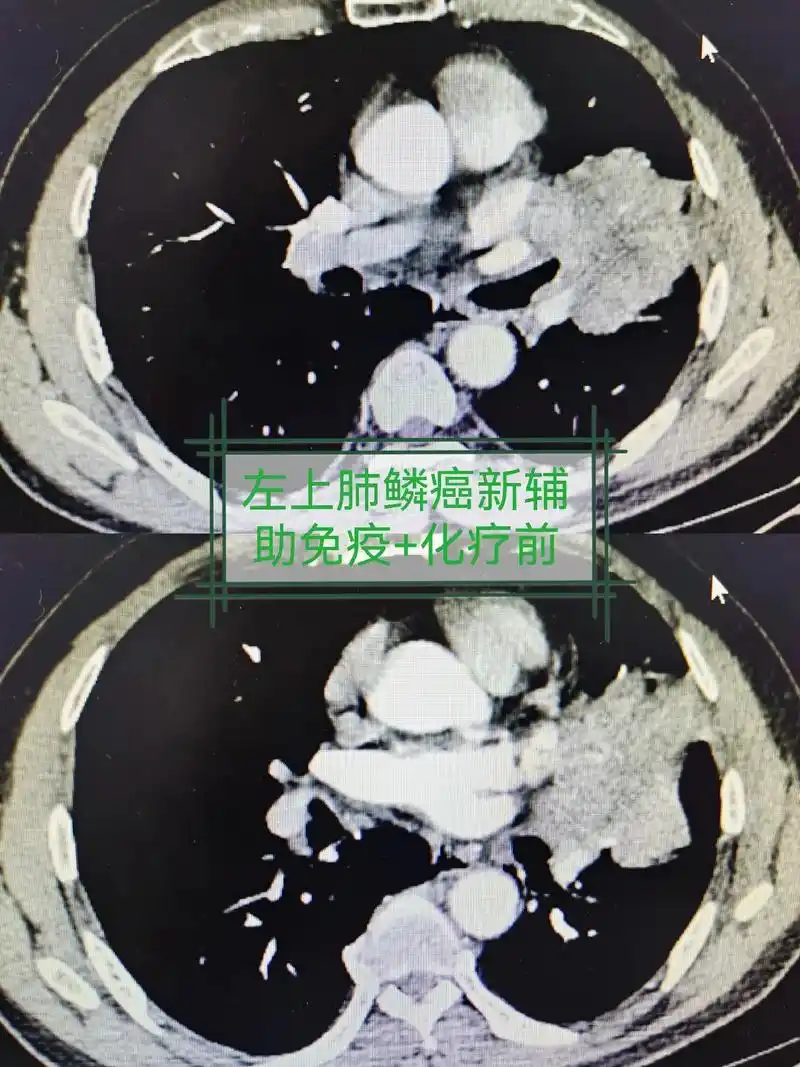

肺癌 #守护健康 #希望能帮到你 局部晚期肺癌,新辅助治疗 - 抖音